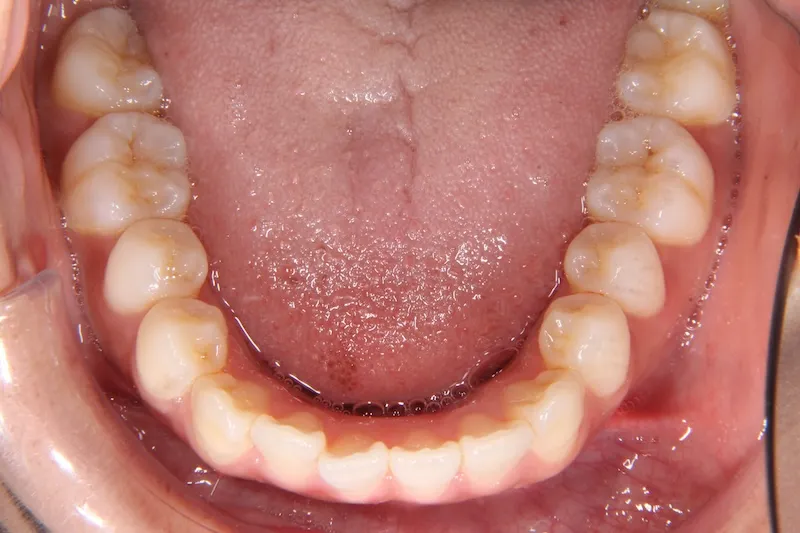

治療経過1